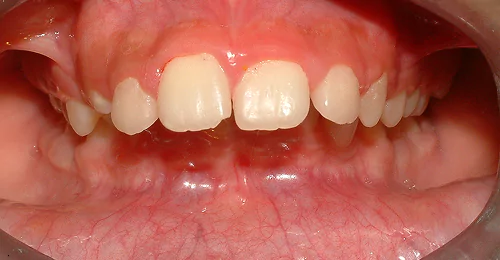

Orthodontic Case – IV

(Case Done by Dr. Sonali Deshmukh M.D.S. / Orthodontist )

Correction of Open Bite

Pre Treatment